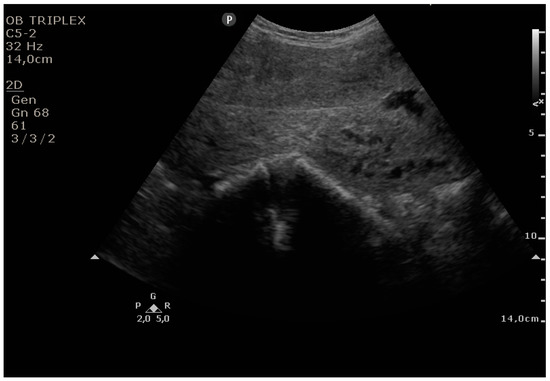

The PUUS method evaluates the proportion of the endometrial length occupied by blood or debris, as follows (Figure 1, Figure 2, Figure 3, Figure 4 and Figure 5):

Grade 2: less than one-half of the endometrial length occupied by blood or debris;

Figure 3. Grade 2: less than one-half of the endometrial length occupied by blood or debris.